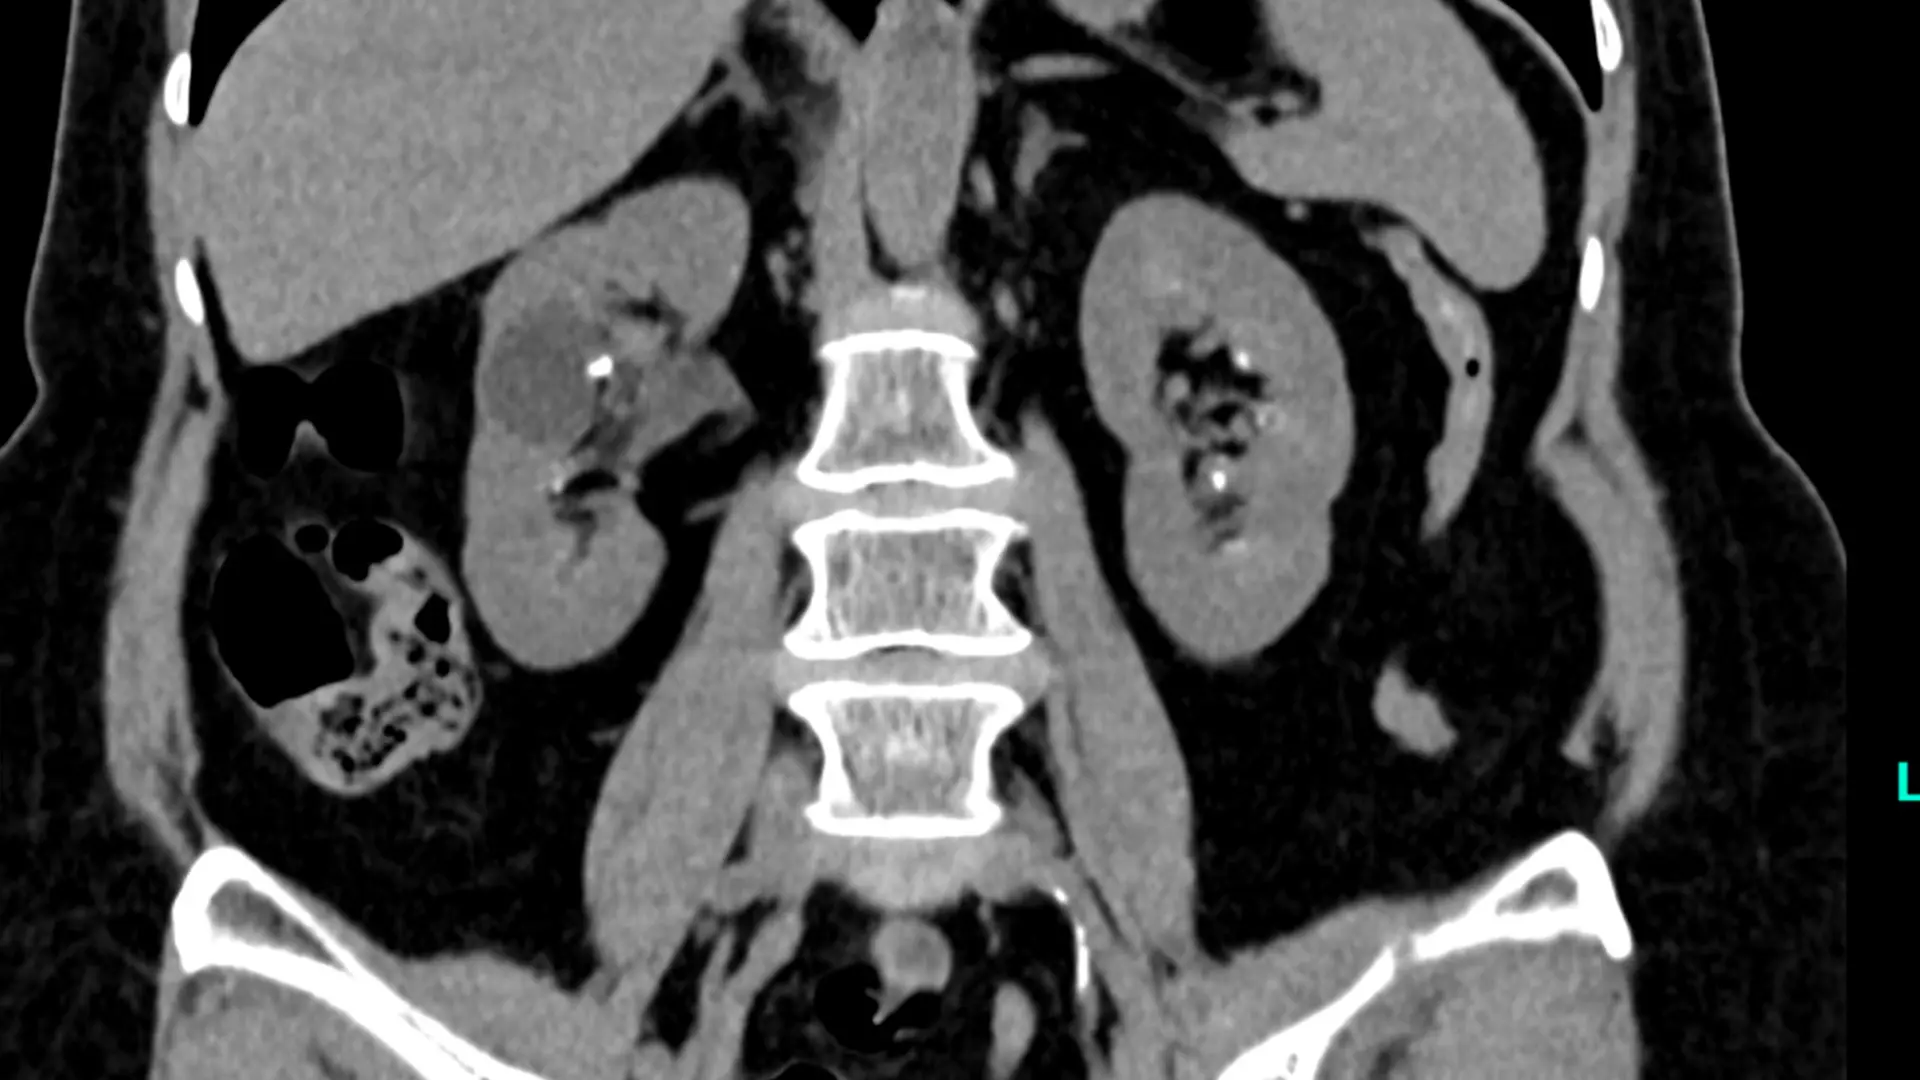

These are two images of a 70-year-old female with bilateral flank pain and more than 20 stones in each kidney was able to be treated with bilateral ureteroscopy and laser lithotripsy without the use of guidewire, sheath, stent, or fluoroscopy with complete treatment of all stones.

A 70-year-old female with bilateral flank pain and more than 20 stones in each kidney was able to be treated with bilateral ureteroscopy and laser lithotripsy without the use of guidewire, sheath, stent, or fluoroscopy with complete treatment of all stones.

Here are two images of the renal stones.